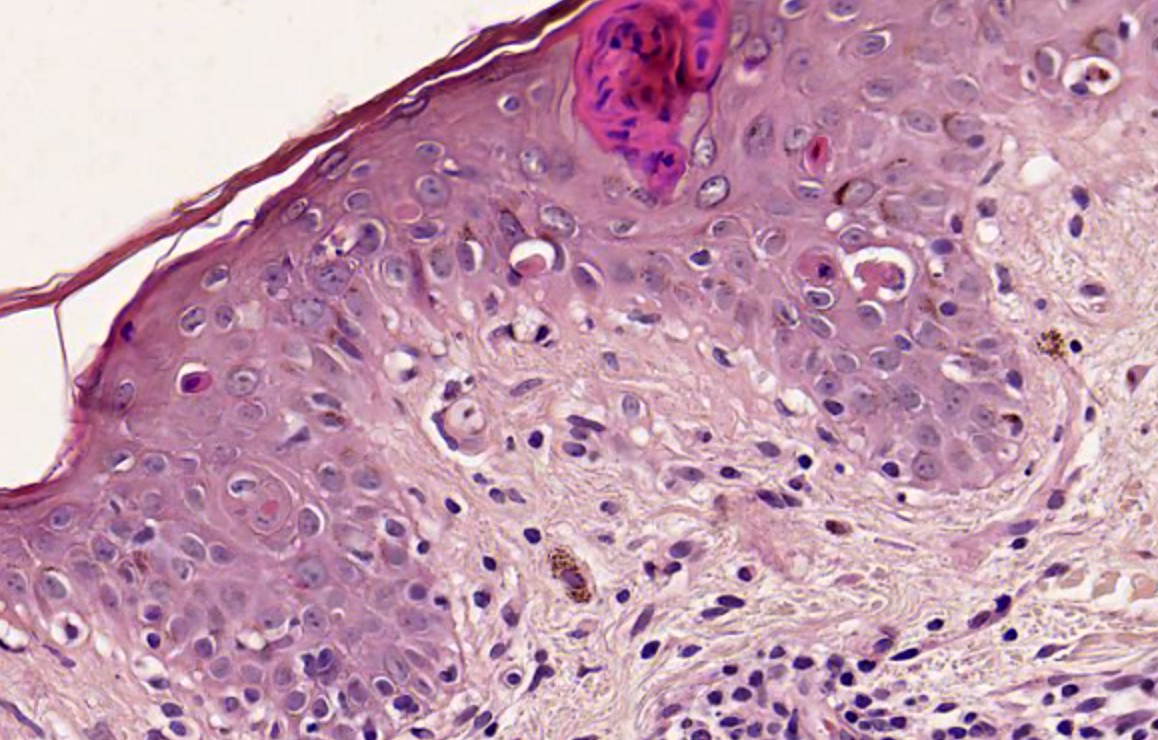

Microscopic (histologic) description

- Interface dermatitis with variable degrees of basal layer vacuolization and scattered cytoid bodies (Lupus 2012;21:577)

- Dyskeratotic keratinocytes extending into upper spinous layers is a very characteristic but rare finding of SCLE (J Cutan Pathol 2001;28:1)

- Hyperkeratosis / parakeratosis may be present

- Sometimes focal hypergranulosis

- Superficial and sometimes superficial and deep perivascular lymphocytic infiltrate (Dermatol Ther (Heidelb) 2021;11:131)

- Dermal mucin, which may be highlighted with Alcian blue or colloidal iron

- Epidermal atrophy, follicular plugging, basement membrane thickening, dermal mucin and pigment incontinence may be present but less prominent than in chronic lupus erythematosus

Microscopic (histologic) images

- Comment: Epidermal thinning with hyperkeratosis. Vacuolar interface dermatitis with dyskeratotic keratinocytes that extend into upper spinous layers. Superficial perivascular lymphocytic infiltrate. Correlate with clinical and laboratory testing. These findings are more consistent with SCLE subtype.

A 35 year old woman presents with multiple nonscarring erythematous annular plaques that arise in photo exposed areas 8 weeks after introducing terbinafine for treatment of onychomycosis. A biopsy of one of the lesions was performed (shown above). What is the most likely diagnosis?

Board review style question #2

A 50 year old man with a history of recent onset hypertension treated with enalapril presented with a 1 month history of annular and erythematous polycyclic plaques with peripheral scale that were located in sun exposed areas. No other systemic manifestations were found. Serologic test results were positive for ANA, anti-Ro / SSA and anti-La / SSB, while negative for ds-DNA, anti-histone and anti-Smith. Which histopathological finding that can be seen in this image is more characteristic of the patient's clinical type?

- Dyskeratotic keratinocytes extending to upper layers

A. Dyskeratotic keratinocytes extending to upper layers